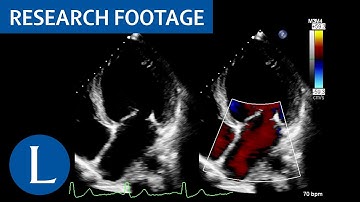

SAX View Interpretation – Wall Motion Patterns #WallMotion #GlobalHypokinesia #RWMA #LVFunction